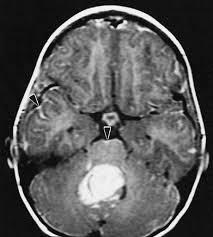

Диагноз опухоли мозжечка может быть поставлен после проведения КТ и МРТ.

Оба метода исследования следует проводить после введения контрастных веществ. На КТ могут помимо опухоли, которая неоднородно накапливать контраст, обнаруживаются кисты и кальцинаты.

На МРТ достаточно неплохо обнаруживаются метастазы, если процедура проведена с контрастированием. Рекомендуется также проведение МРТ спинного мозга для исключения опухолевого процесса в нем.